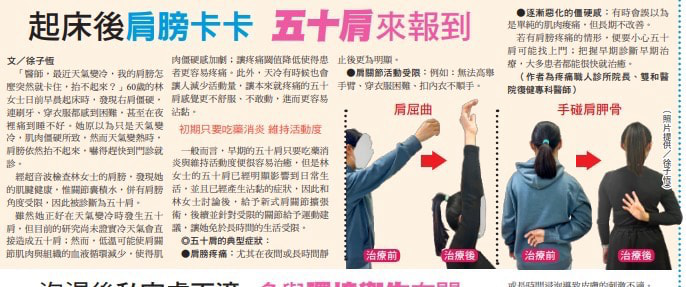

五十肩最典型的症狀就是肩膀疼痛、僵硬與活動受限。而且症狀通常持續一段時間。